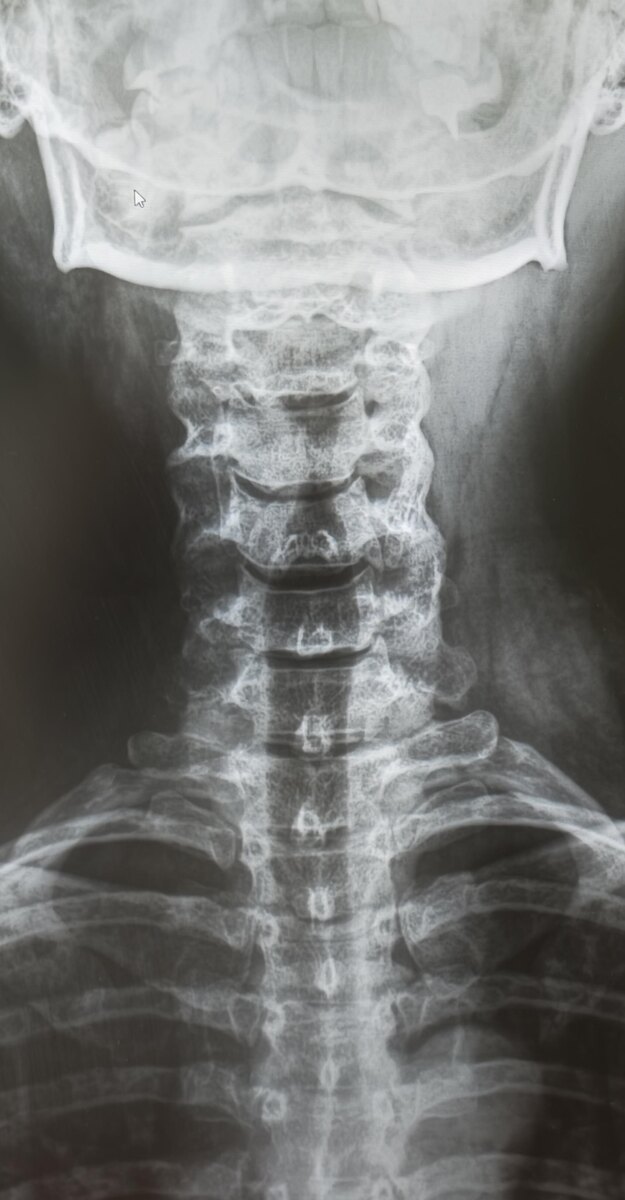

На днях просматриваю снимки шейного отдела позвоночника молодой пациентки, направлена с диагнозом-цервикалгия(боль в шейном отделе позвоночника).

На снимках, кроме кифотической установки в шейном отделе позвоночника, незначительного неравномерного сужения межпозвонковых щелей и не выраженного заострения унковертебральных отростков, патологии не выявлено. Однако взгляд цепляется за турецкое седло.

При измерении размеров турецкого седла получаются показатели: глубина 13.9мм, передне-задний(сагиттальный)-20.4мм. Нормальные размеры турецкого седла у взрослого: cагиттальный размер (передне-задний) 10–15 мм. Глубина 8–12 мм.

Заключение: Начальные проявления остеохондроза шейного отдела позвоночника. Унковертебральный артроз. Кифотическая установка шейного отдела позвоночника. Увеличение размеров турецкого седла-признак аденомы гипофиза.

Рек-но: дообследование- МРТ головного мозга, конс. нейрохирурга.